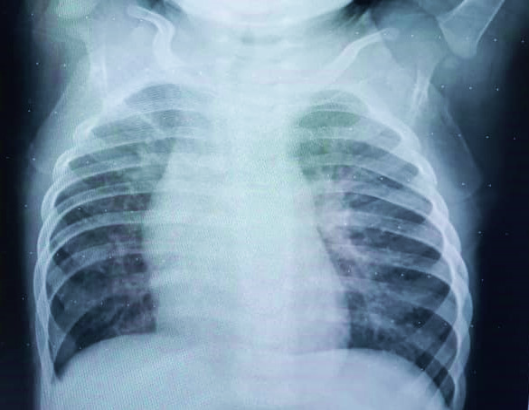

Echocardiogram (Figure 2):

Figure 2 Echocardiogram. Double barrel image.

Transposition of the great vessels with closed ventricular septum, Boston type III, Aorta to the right and slightly anterior to the pulmonary. 15mm balloon atrioseptostomy with left to right shunt. Moderate tricuspid regurgitation with TAPSE = 18mm.

After three months of convalescence and without evidence of sequelae from the viral infection, surgical intervention was decided. Mustard surgery was performed for definitive physiological correction, with extracorporeal circulation time of 113 minutes, aorticclamping time of 62 minutes at 23 degrees of temperature and modified hemofiltration once the extracorporeal circulation had concluded. Antimicrobial prophylaxis was used for 24 hours with Ceftriazone.